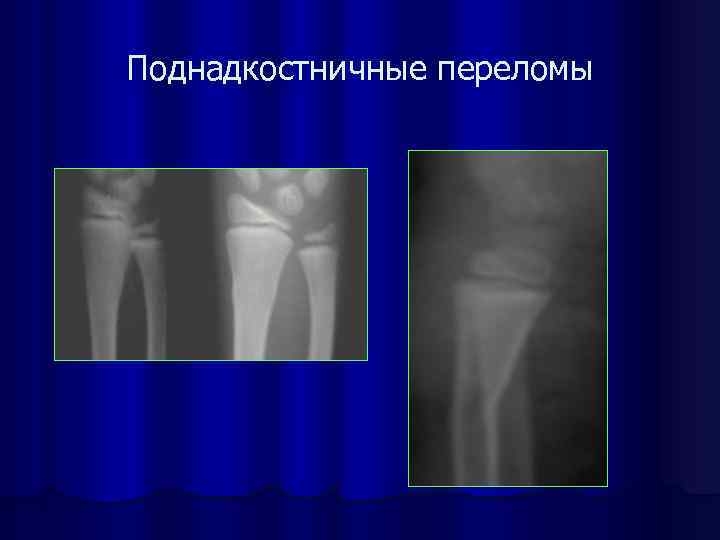

Поднадкостничные переломы